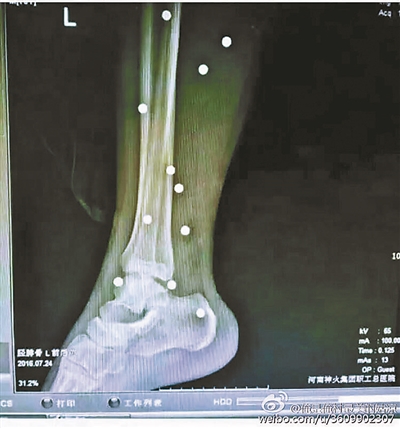

傷者體內(nèi)取出的鋼珠

爆炸導(dǎo)致鋼珠遍布傷者身體各處

黃明的伯伯對北青報記者表示,由于黃明直接踩到了爆炸物,所以傷情最為嚴(yán)重,“他的腿被炸斷,身體內(nèi)被炸進(jìn)了40多顆鋼珠。手術(shù)后已經(jīng)從體內(nèi)取出29顆鋼珠,還有十多顆鋼珠沒有取出來?!备鶕?jù)黃明的入院記錄,他全身有多處爆炸傷,且全身多處異物存留。

爆炸發(fā)生時,陳浩的位置與黃明靠得很近,因此也受傷較重。他告訴北青報記者,經(jīng)過10多個小時的手術(shù)后,醫(yī)生從他身體里取出了12顆鋼珠。目前,他和黃明兩人經(jīng)過手術(shù)后,已從重癥監(jiān)護室轉(zhuǎn)至普通病房。其余三人中,陳剛的臀部受傷,當(dāng)天晚上在醫(yī)院清理完傷口后便回了家,而同行的兩名女生身上有一些擦傷。